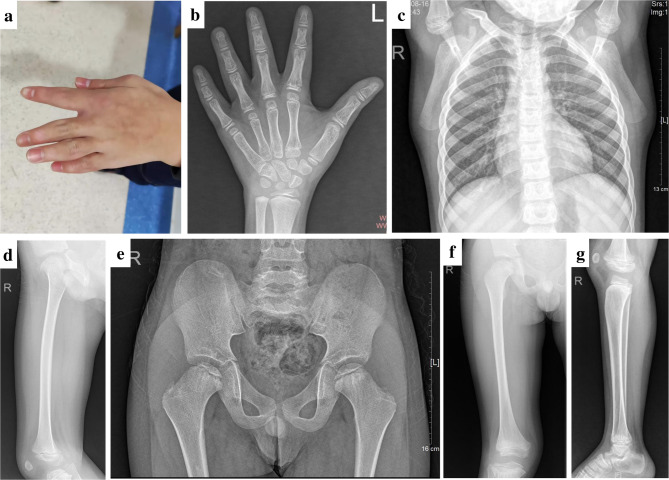

Case presentation: A boy first evaluated at 9 years and 10 months for short stature was diagnosed with compound heterozygous mutations in PLEC, CD96, and RNU4ATAC genes, with comorbid congenital multiple epiphyseal dysplasia and growth hormone deficiency. These mutations collectively contributed to severe short stature, skeletal deformities, and delayed neurodevelopment. Orthopedic surgeries were performed at 9 years and 10 months (first intervention), 11 years and 6 months (second intervention), and 12 years and 9 months (third intervention), while growth hormone therapy (GHT) was initiated at 11 years and 10 months. Over 25 months of GHT, his height increased by 18 cm, bone age advanced by five years, and gait improved. Final clinical evaluation at 13 years and 11 months confirmed sustained improvements in height (137 cm) and motor function.

Conclusion: This case involves a child with short stature caused by rare mutations of PLEC, CD96, and RNU4ATAC. This is the first case report documenting the concurrent presence of all three rare mutations. Orthopedic surgery and GHT were employed to improve the patient's development and quality of life. We propose that early identification of high-risk factors, genetic screening, and comprehensive treatment can enhance therapeutic effectiveness and improve the patient's quality of life.